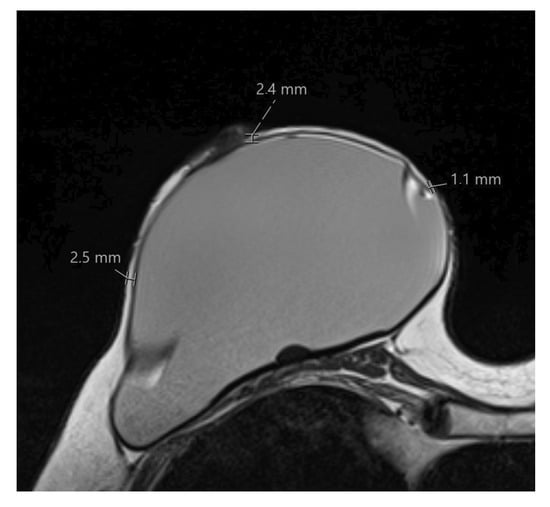

2.3. MRI Data Analysis

- Skin flap thickness at 2, 3, 4, 6, 8, 9, 10, and 12 o’clock as well as retromamillary area;